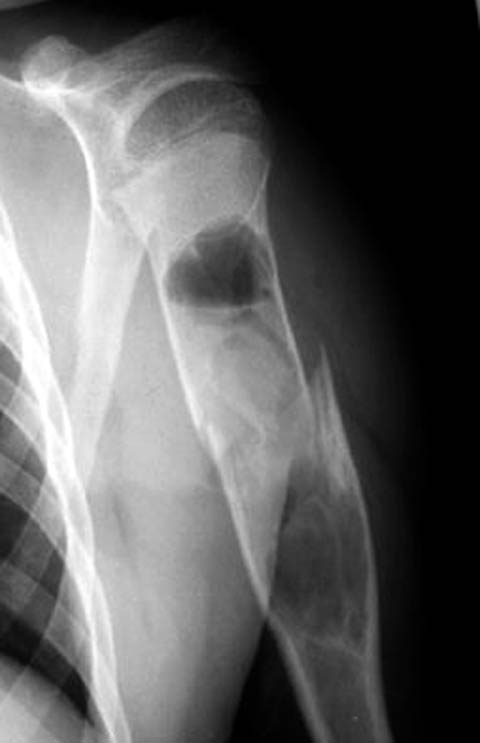

Дифференциальную диагностику надо проводить между однокамерной костной и аневризмальной кистой, но расположение в полости кисты тонкого,

линейного фрагмента кости, подтверждает диагноз однокамерной костной кисты.

"Упавший" фрагмент - патогномоническая подсказка к патологическому перелому, часть стенки падает в полость кисты и опускается вниз из-за

силы тяжести.

Подозрение о "шаровидной полости" в головке - это из-за укладки, и на представленном снимке подтверждение правильности рекомендации коллег.